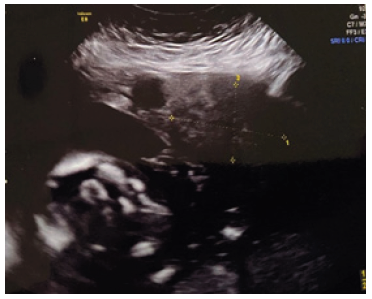

40-year old woman (gravida 4, part 3, abort 1) presented at 34 weeks of gestation for her first pediatric surgery routine antenatal care visit. She had history of preeclampsia; a pelvic ultrasound was performed owing of her prenatal history a cystic mass measuring 4.6X3.6X3.4 cm was incidentally found adjacent to the upper pole of the left fetal kidney (Figure 1). Ultrasound control was performed and revealed the mass to be larger and more solid appearing. Finally, an ultrasound examination at 39 weeks of gestation revealed oligohydramnios and inability to evaluate the left fetal kidneys. Subsequently, the mother underwent an abdominal cesarean delivery of a healthy boy of 3.4kg. APGAR score was 9 and 10 at 1 and 5 minutes, respectively. Physical examination was normal other than a large mass was palpable on upper pole of the left kidney. Postnatal ultrasound examination showed a predominantly solid suprarenal mass deforming the upper pole of the left kidney. The scan demonstrated alteration of kidney structure and displacement of the spleen and intestinal structures (Figure 2). Serum electrolytes, complete blood count, ferritin, and transaminase and catecholamines were normal. Urinalysis and sensitivities of tumor marker levels were normal. Therefore, the patient was admitted to an abdominal exploration with the most probable diagnosis at this stage of a cystic neuroblastoma or an adrenal hematoma as main differential diagnosis.

Figure 1: Prenatal sonogram with cystic mass.